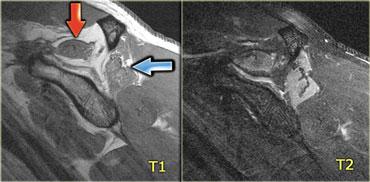

Cơ khuỷu trên ròng rọc phụ (mũi tên đỏ) – Thần kinh trụ tăng tín hiệu gợi ý viêm thần kinh trụ (mũi tên xanh)

Hình bên trái là hình ảnh khớp khuỷu, mặt trong nằm ở bên trái.

Lưu ý có một cơ nằm ngay phía sau thần kinh trụ, trong điều kiện bình thường cơ này không hiện diện tại vị trí này.

Đây là cơ khuỷu trên ròng rọc phụ (accessory anconeus epitrochlearis), gặp ở khoảng 10% dân số.

Đây là nguyên nhân thường gặp gây viêm thần kinh trụ do chèn ép, biểu hiện bằng đau và tê bì mặt trụ của bàn tay, đôi khi kèm teo cơ mô út và mô cái.

Cần quan sát kỹ thần kinh trụ khi phát hiện cơ phụ này.